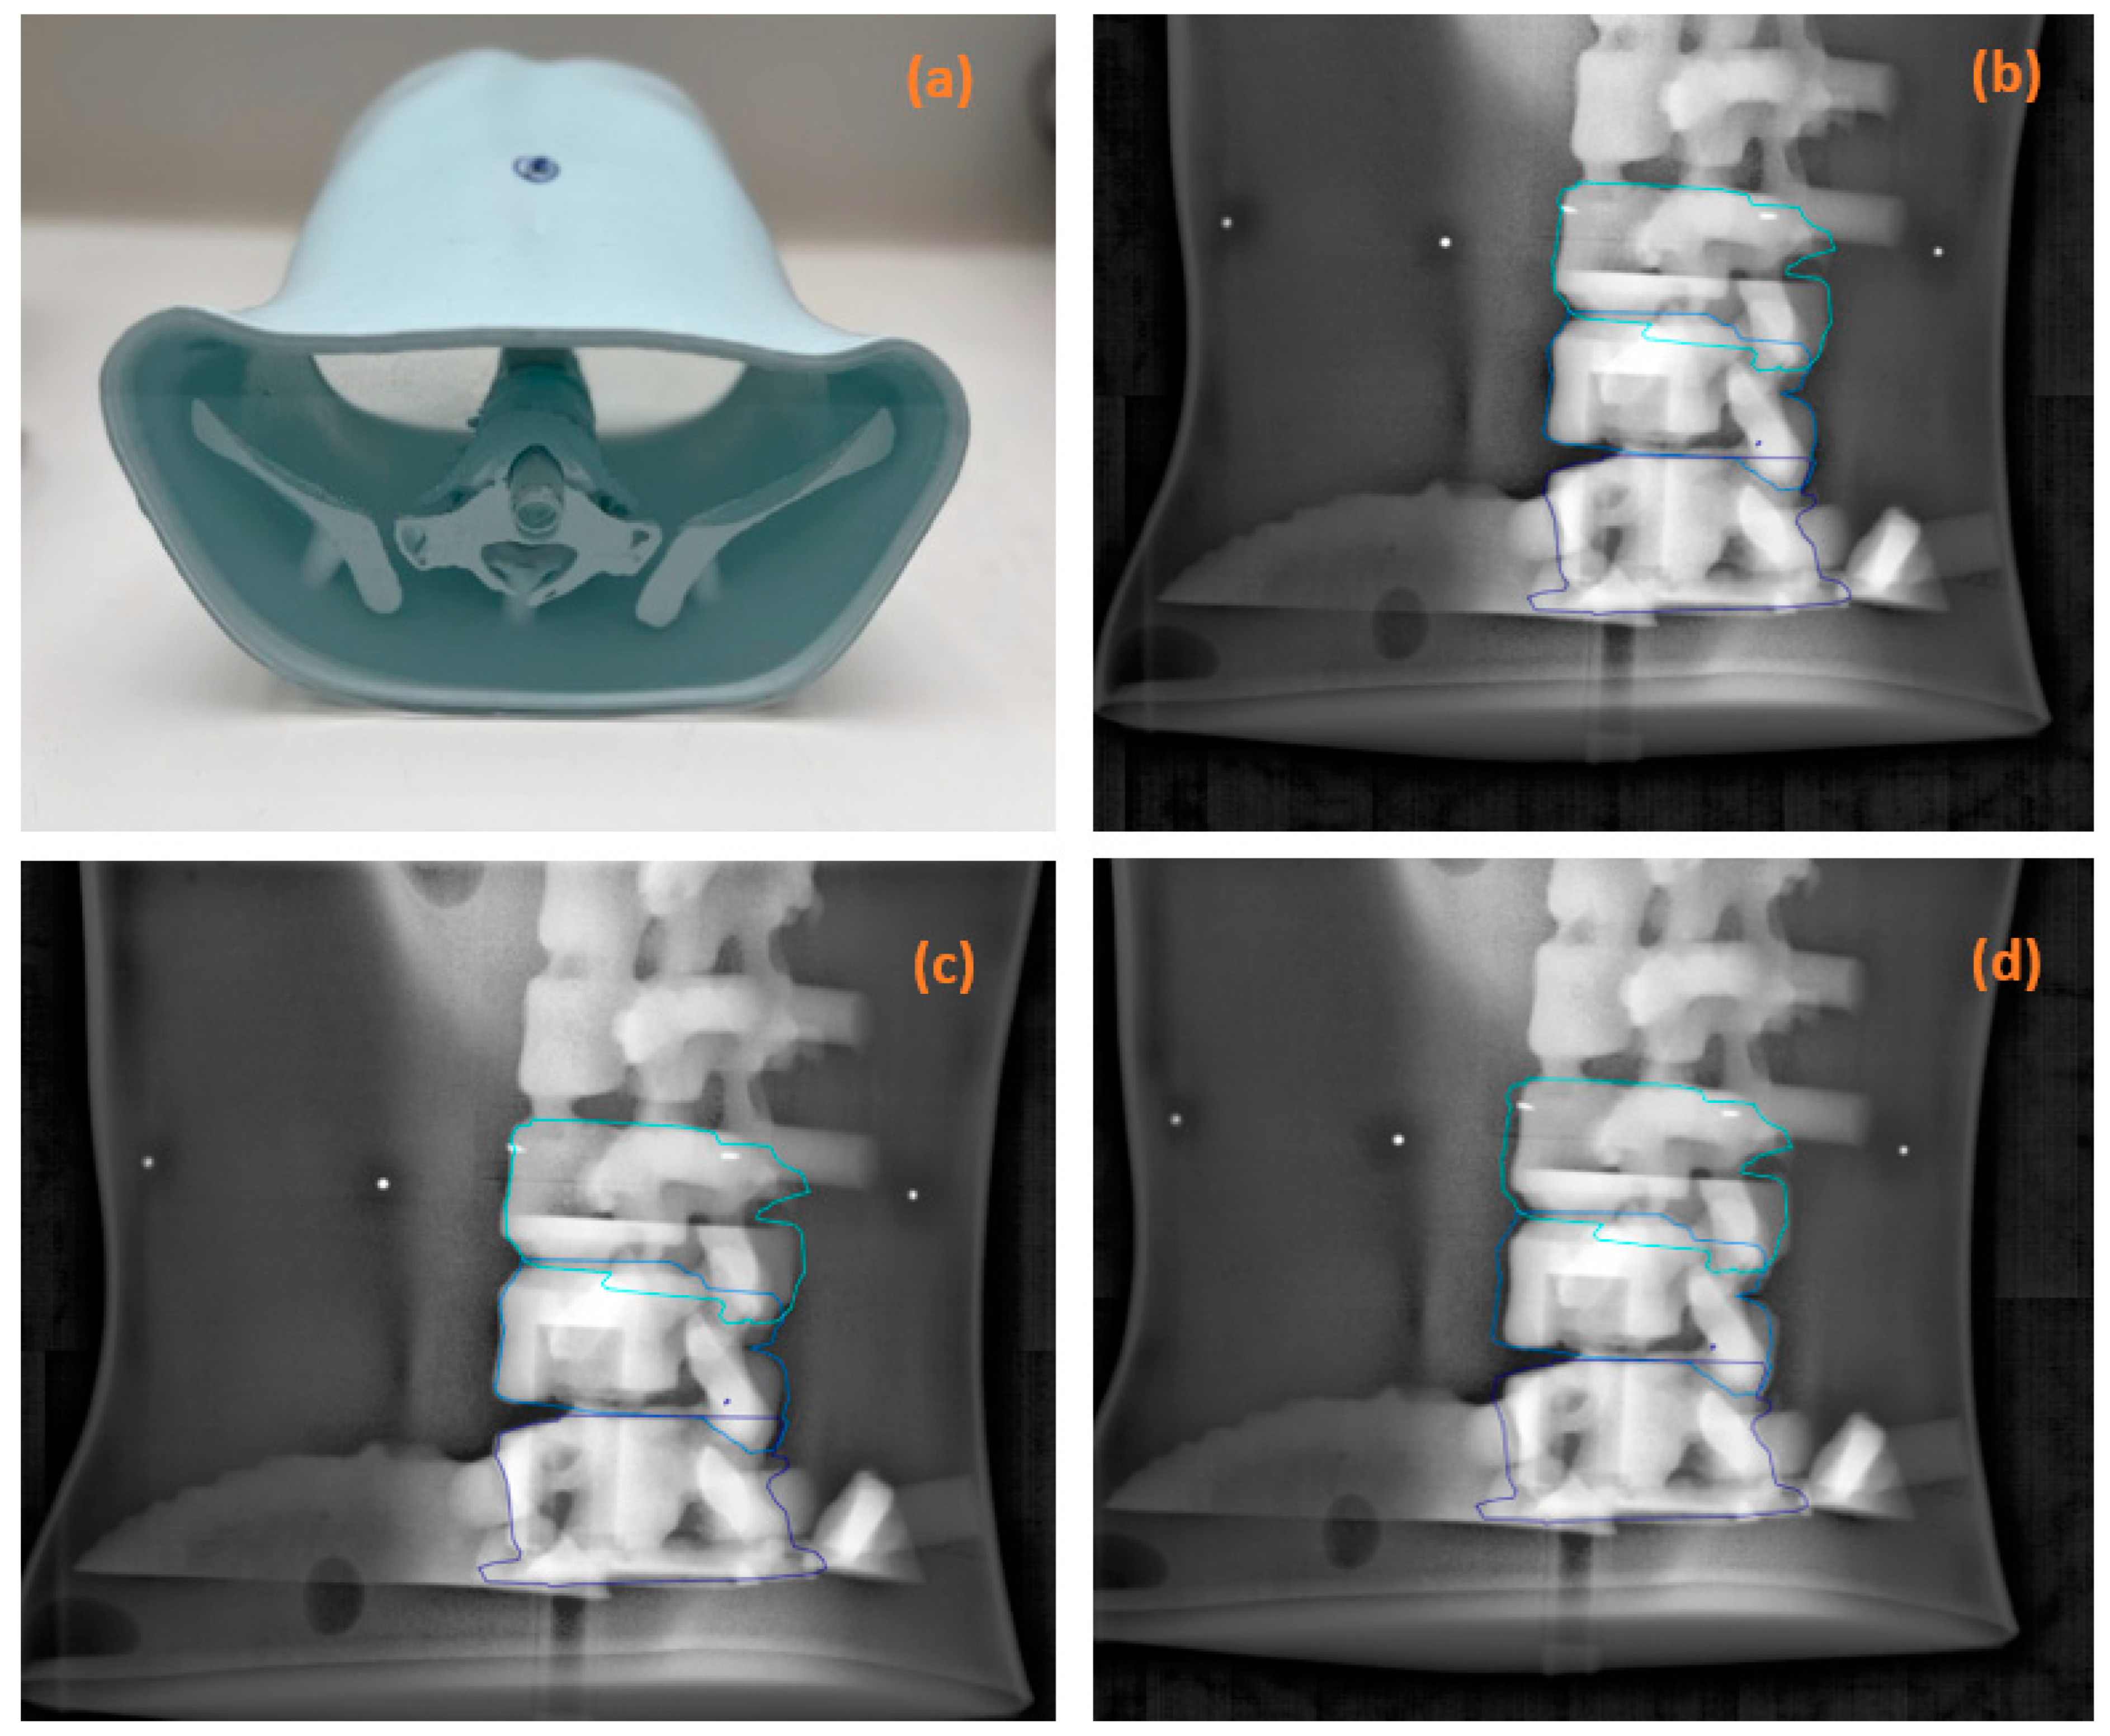

2.1. Phantom Study

3.1. Phantom Study